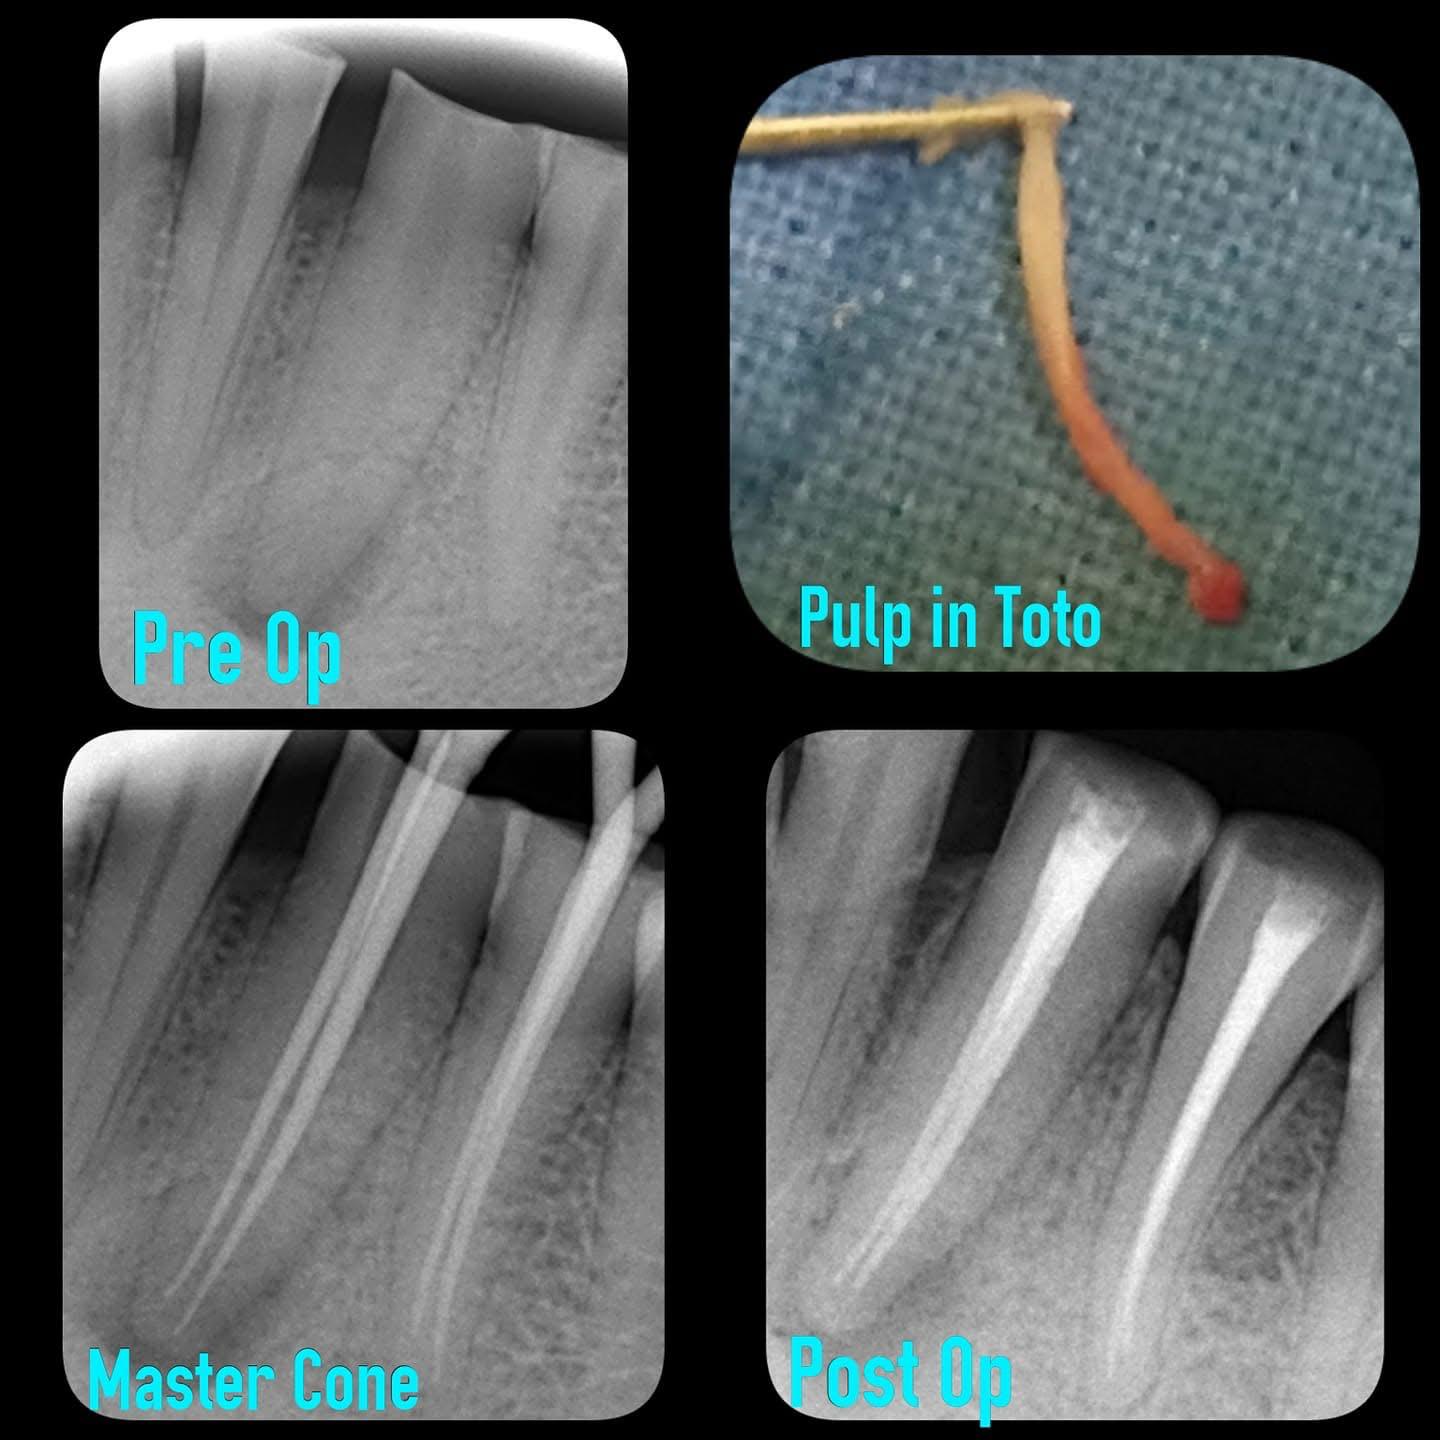

Root Canal Treatment

Clinical Cases